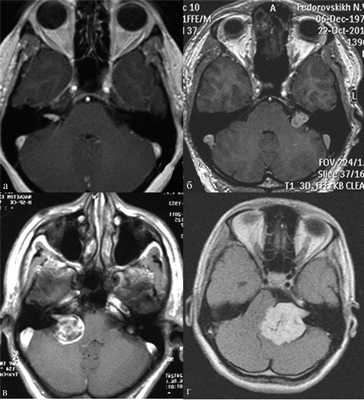

Наиболее информативным методом выявления вестибулярных шванном является МРТ головного мозга с контрастным усилением в режиме Т1 и Т2. Это исследование позволяет определить размеры опухоли, наличие перитуморозного отека, наличие признаков окклюзионной гидроцефалии, которая может быть следствием сдавления опухолью IV желудочка. Кроме этого МРТ позволяет провести дифференциальную диагностику с другими опухолями схожей локализации (чаще с менингиомой задней грани пирамиды височной кости). Еще одним стандартом диагностики является КТ в костном режиме. Независимо от снижения слуха стандартом является проведение аппаратной аудиографии.

Рис. 1.Иллюстрация классификации неврином слухового нерва по Koos. а — I стадия — опухоль находится в пределах внутреннего слухового прохода, диаметр экстраканальной части составляет 1—10 мм; б — II стадия — опухоль вызывает расширение канала внутреннего слухового прохода и выходит в мостомозжечковый угол, ее диаметр составляет, 11—20 мм; в — III стадия — опухоль распространяется до ствола головного мозга без его компрессии, диаметр составляет 21—30 мм; г — IV стадия — опухоль вызывает компрессию ствола головного мозга, ее диаметр более 30 мм.

Рис. 2.Классификация неврином слухового нерва по M. Samii. а — Т1 — интрамеатальная опухоль (рис. 2, a); б —Т2 — интра-экстрамеатальная опухоль; в — Т3а — опухоль заполняет мостомозжечковую цистерну; г —Т3b — опухоль распространяется до ствола головного мозга; д —Т4а — опухоль вызывает компрессию ствола; е —Т4b — опухоль грубо деформирует ствол мозга и IV желудочек.